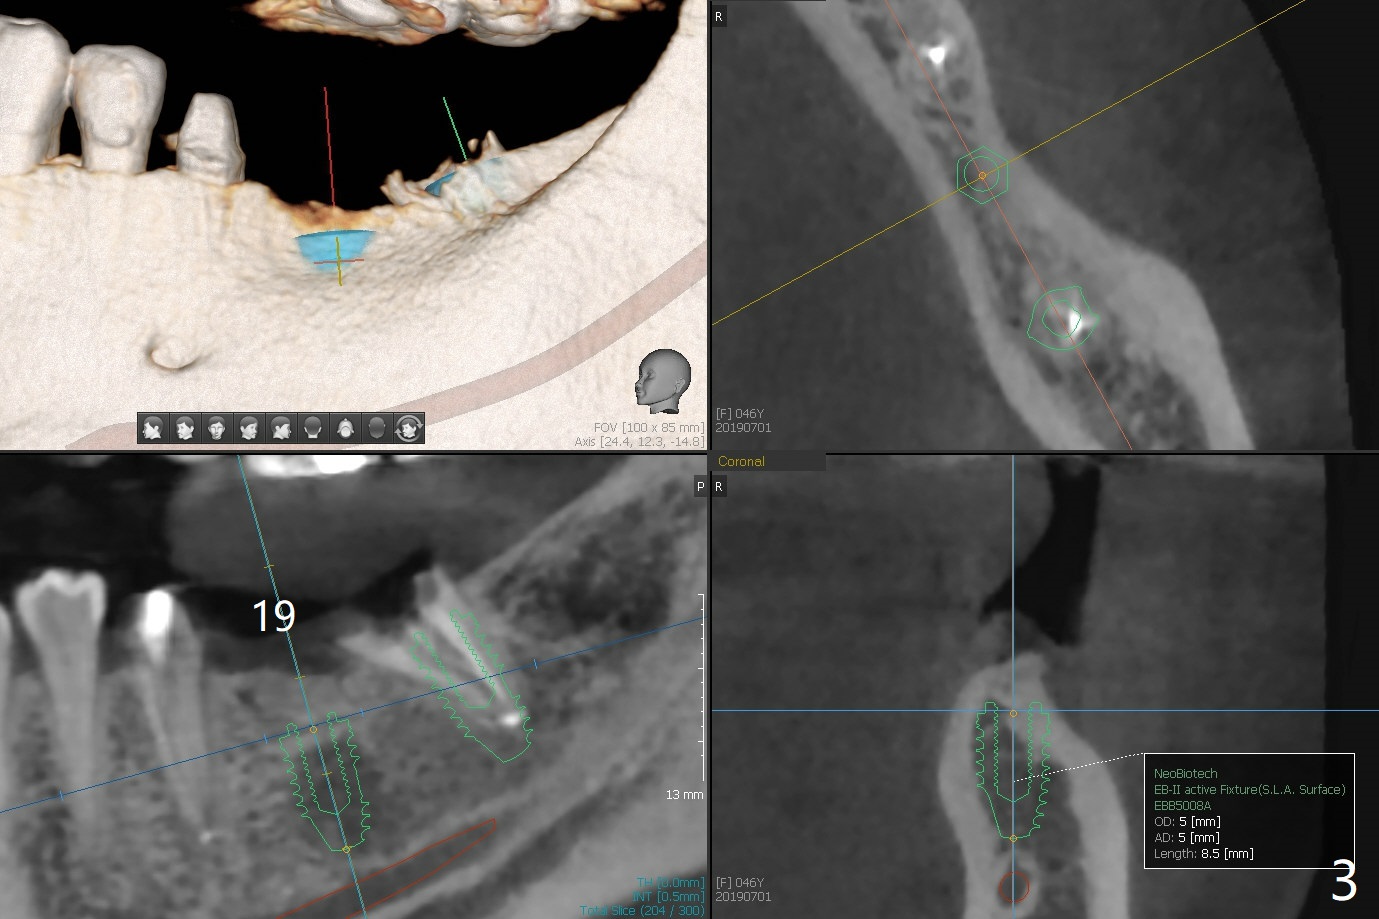

A 46-year-old woman has a failed FPD 18-20 (Fig.1). To have thicker buccal bone, the 5 mm implants at #18 (Fig.2) and 19 (Fig.3) seem to be a little large. Smaller (4.5 mm) will be more appropriate so that the coronal threads of the implant at #18 will be more securely covered by the regenerating bone. In the same manner, the implant to be placed in the healed site of #19 will have more buccal bone when the diameter of the implant reduces.